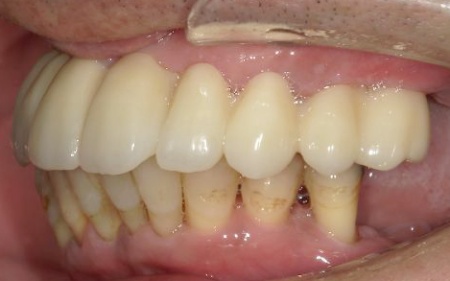

①上の歯7本、右下の奥歯2本を抜歯する。上あごには抜歯と同時に4本のインプラントを埋め、その上に10本分の仮歯を取り付けるオールオンフォーを行う。

インプラントの種類には、あごの骨と結合する力に優れたオステム社のETⅢを採用。インプラントが骨にしっかり定着するまでの間は、通常のインプラントよりも細い暫間インプラントを一時的に併用して仮歯を支える

②インプラントが安定したことを確認してから、仮歯を外して最終的な人工歯を装着する

最後に、残っている下の歯としっかりと噛み合っていることを確認し、治療を終了しました。